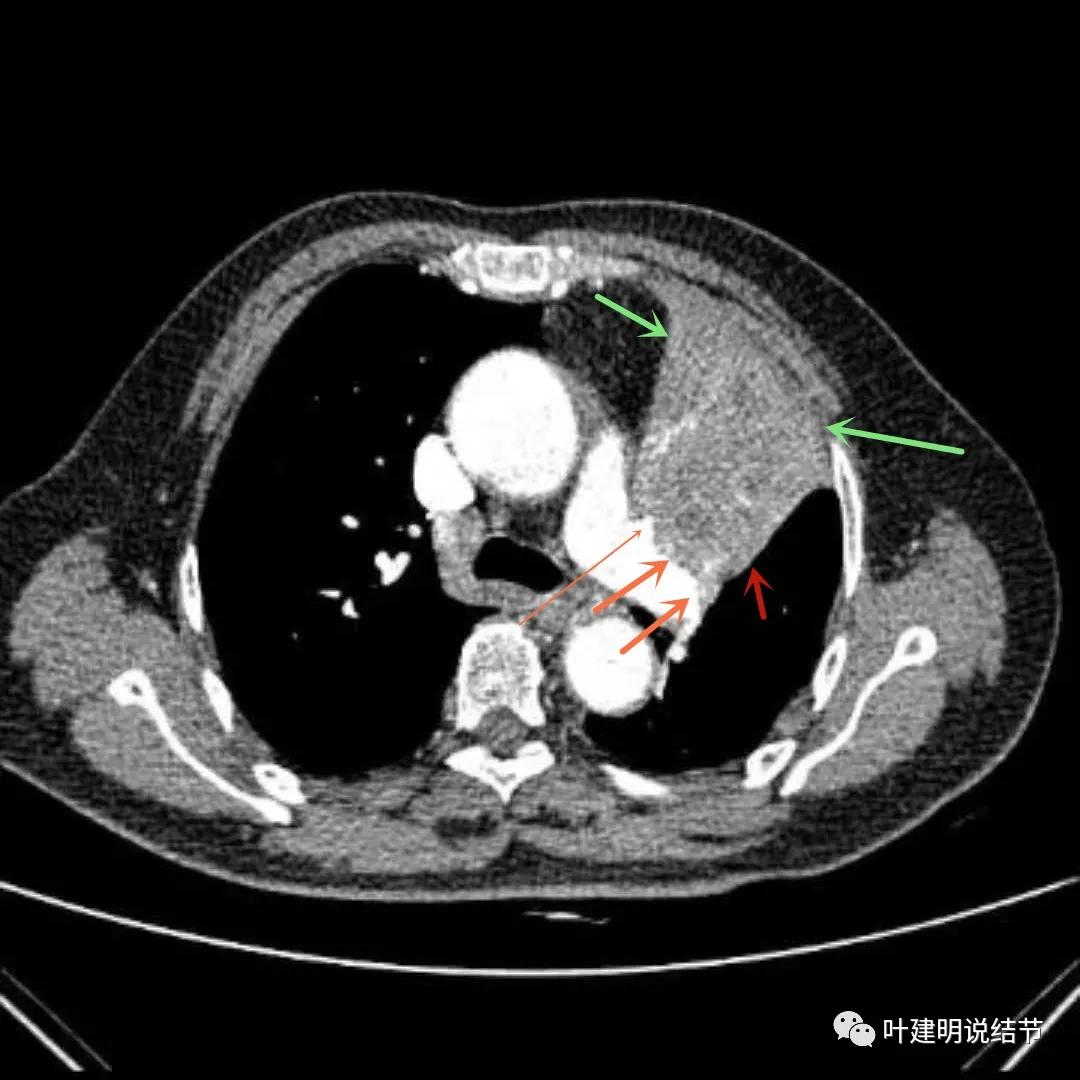

上图绿色箭头所指区域考虑为肺不张,红色示肿瘤处,桔色箭头所指处是被肿瘤包绕的肺动脉分支

上图绿色箭头所指区域考虑为肺不张,红色示肿瘤处且有不均质与膨胀性,桔色细箭头所指处是被肿瘤包绕的肺动脉分支起始部,粗桔色箭头示肺动脉与肿瘤间紧密愈着,考虑有侵犯肺动脉